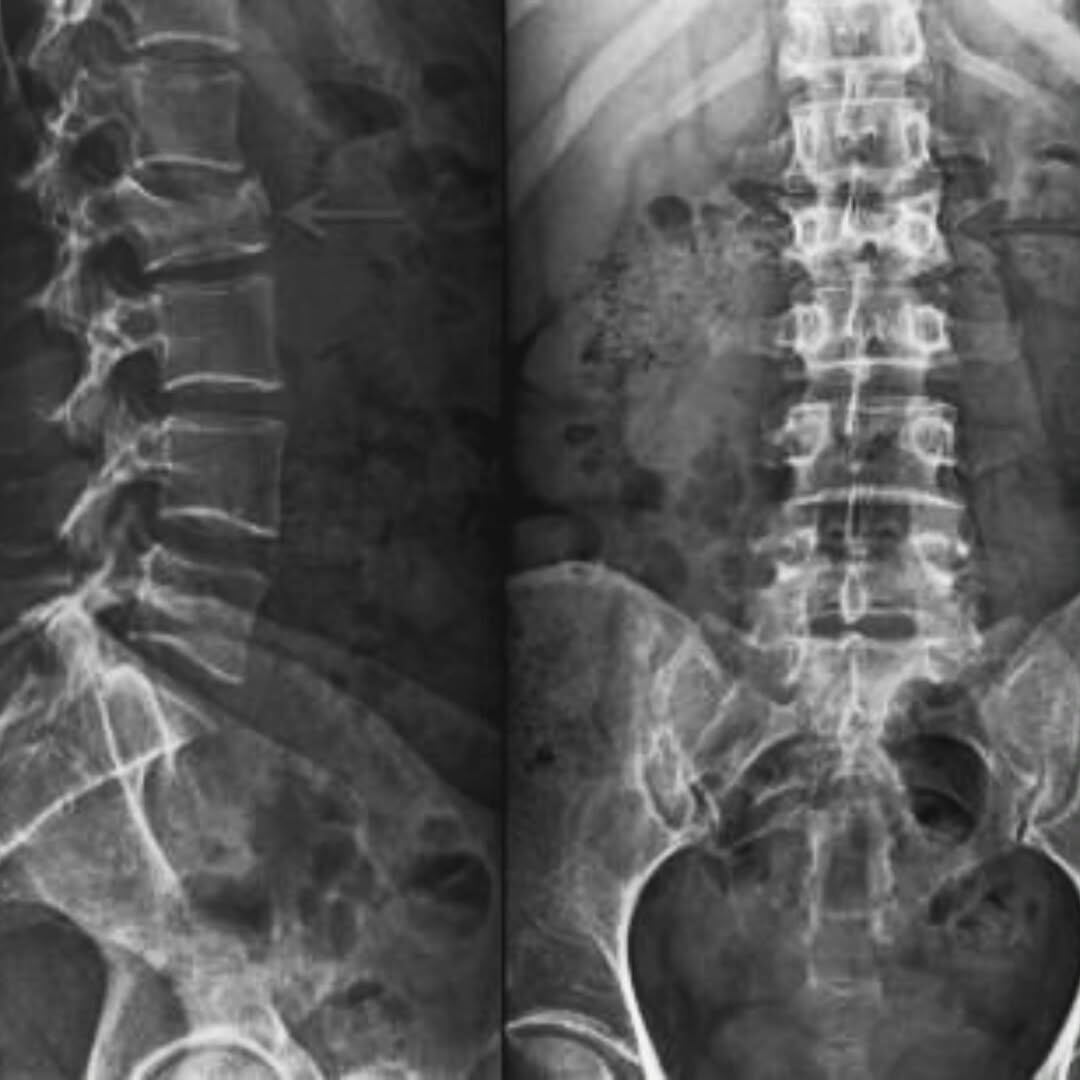

Producto del cansancio, según reconoció en aquel momento, se durmió y su carro fue a dar a una cuneta. El vehículo quedó en pérdida total por la magnitud del golpe y él resultó con lesiones serias, principalmente en la espalda.

“Una fractura en la columna me dejó postrado en una cama, sin saber si podría volver a levantarme. Fue la ayuda de Dios y el amor incondicional de mi familia lo que me devolvieron las fuerzas para seguir adelante”, agregó.